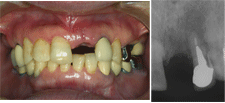

もし自分が酔っぱらって転倒し、上顎前歯を1本折って欠損になったとしたら、絶対にブリッジではなく、1ピースAQBを1本植立してもらい、メタルボンド冠で直そうと思う。

植立後約19年の症例を筆頭に多数のAQB長期経過症例のメインテナンスを日頃担当している筆者の診療所のスタッフも恐らく同じ選択をするであろう。

それ程欠損補綴で信頼に足るすばらしい治療法として臨床的に実証されているので、やはり広く国民にその恩恵を提供したいと思うわけである。